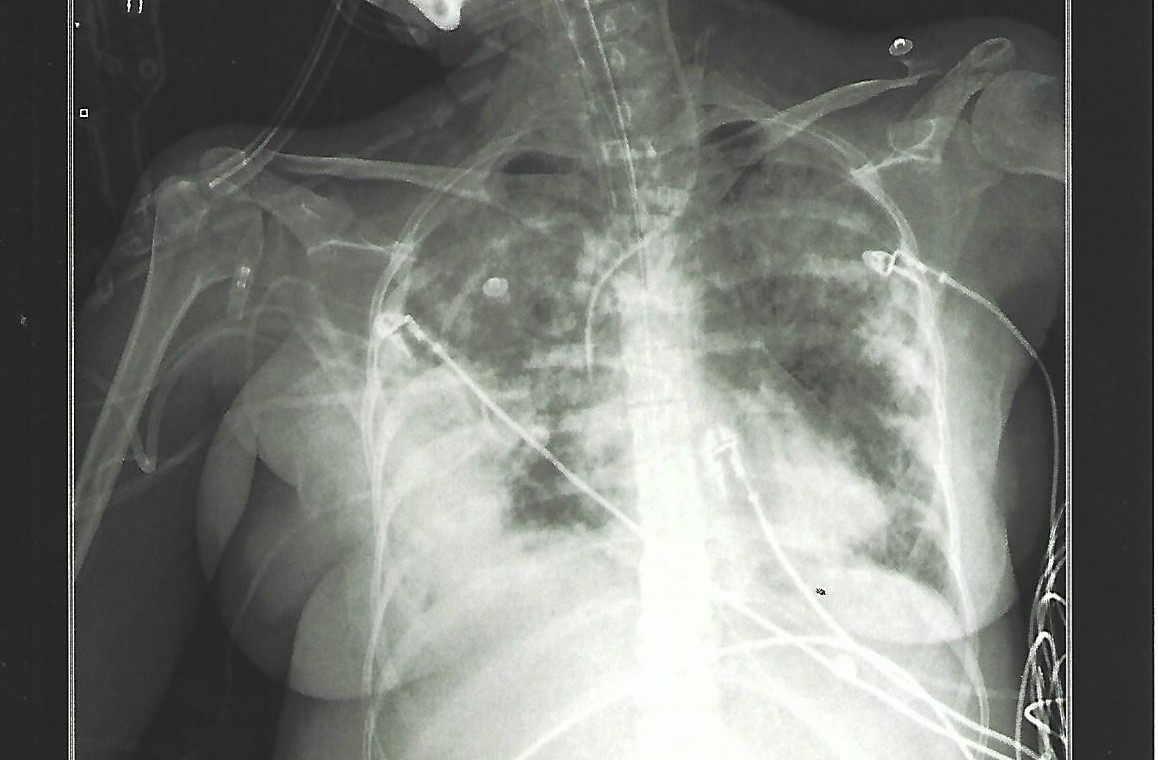

Ce récit est la chronique de dix-sept jours dans une unité de soins intensifs, en 2018, à cause d’un Syndrome de Détresse Respiratoire Aigüe (ARDS), insuffisance respiratoire aiguë secondaire à une inflammation sévère affectant les poumons. Ce même syndrome qui, deux ans plus tard, conduira aux soins intensifs les patients les plus sévèrement atteints par la COVID-19.